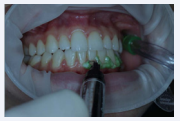

Next, OptraGate (Ivoclair Vivadent, Amherst, NY, USA) was used to ensure relative isolation and to provide a full view of the anterior and posterior teeth, and Lase Protect (DMC Equipments, São Carlos, SP, Brazil) was applied at the contour of the gingival tissue in an attempt to avoid the contact between the bleaching gel and the gingiva (Figure 3).

Relative isolation performed using OptraGate (Ivoclair) and gingival  protection using Lase Protect (DMC Equipments).

Figure 3 Relative isolation performed using OptraGate (Ivoclair) and gingival protection using Lase Protect (DMC Equipments).

Tooth bleaching has become popular in dentistry, and people have been increasingly requesting for this cosmetic treatment. The patient from the present case report was young and her teeth were not extremely darkened (Figure 2), as a B2 color shade is one of the whitest possible shades. However, the patient was anxious for having whiter teeth. Considering that only a yellowish staining pattern was present, the in-office tooth bleaching regimen was suggested, which was promptly accepted by the patient. In-office regimens generally results in faster whitening effect, mainly due to the high concentrated gels used when compared to the home-use regimen, which uses materials with low peroxide concentration but during higher periods of application [11]. Bleaching agents act by an oxidation process of the pigments adhered to the enamel or dentin substrates [12] or by oxidizing the dental organic matrix [13]. Consequently, they act by contact, and according to previous reports bleaching agents are powerful substances that may produce allergenic reactions when they enter in contact with soft tissues, mainly gingiva and lips [14,15]. Thus, two protective products were used in the present case report: the OptraGate and the gingival barrier Lase Protect (Figure 3), which had satisfactorily protected the lips and the gingival tissues, respectively.